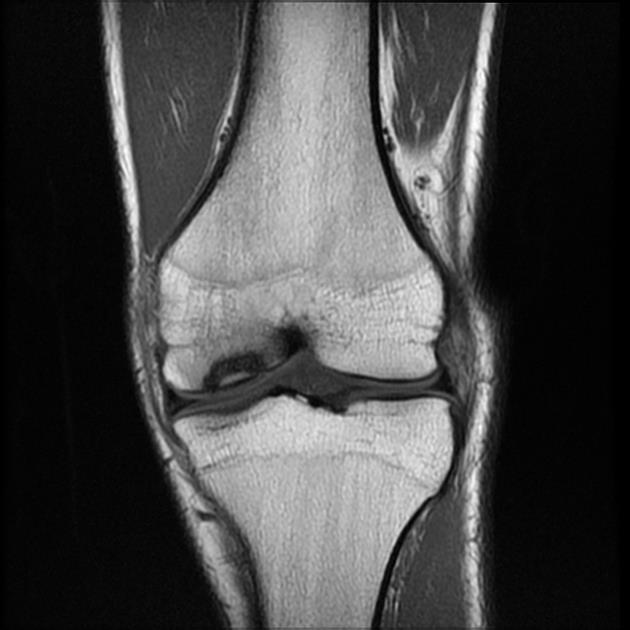

Специфическим признаком РВС является остеохондрит Вегенера - поражение длинных трубчатых костей на границе эпифиза и диафиза, обусловленное нарушением образования кальция и торможением развития остеобластов. Выделяют три степени остеохондрита. Характерными для РВС являются II и III степени. Наряду с остеохондритом, у детей грудного возраста часто обнаруживаются периостальные наложения при рождении и в первые месяцы жизни, поражающие длинные трубчатые кости и череп. Остеохондриты и периоститы обнаруживаются симметрично в нескольких костях. Возможно развитие гумм в метафизах и диафизах, вызывающих переломы и псевдопаралич Парро. При этом наблюдается локальная болезненность и отек в зоне поражения. Конечность выглядит парализованной, но чувствительность и движения пальцев сохранены. Возможно развитие фалангитов или дактилитов с деструктивными гуммозными и периостальными изменениями [1, 5, 29]. Данные поражения протекают безболезненно и не образуют свищей. По нашим данным, самым частым признаком РВС на сегодня является поражение костей. У 43 (56,6%) больных был диагностирован остеохондрит II степени, а у 3 (3,9%) - III (рис. 4, а, б). Рисунок 4. (а, б). Остеохондрит II степени у новорожденного с РВС. Часто выявлялись периоститы трубчатых костей, сочетающиеся с остеохондритами II степени (рис. 5, а, б). Рисунок 5. Сифилитический диффузный остиомиелит трубчатых костей (внутриметадиафизарный перелом проксимального отдела плечевой кости) до проведения специфической терапии (а) и после лечения (б). Псевдопаралич Парро наблюдался у 1 ребенка (рис. 6). Рисунок 6. Псевдопаралич Парро левой руки у ребенка 1,5 мес с РВС. Также у 1 ребенка, поступившего в возрасте 2,5 мес, диагностирован остеохондрит II степени, периостит, эпифизарная гумма фаланги II пальца кисти и фалангит, возникающий то на одном, то на другом пальце.

Ранний врожденный сифилис обычно проявляется в течение первых 3 месяцев, жизни. Манифестация включает характерные везикуло-буллезные высыпания или пятнистую медно-красную сыпь на ладонях и подошвах и папулезные поражения вокруг носа и рта и в области подгузников, а также петехиальные высыпания. Часто развиваются генерализованная лимфаденопатия и гепатоспленомегалия. Ребенок может плохо расти и иметь характерные слизисто-гнойные или кровянистые выделения из носа, вызывающие заложенность носа. У некоторых младенцев развивается менингит, хориоидит, гидроцефалия или судороги, у других может развиваться умственная отсталость. В течение первых 8 месяцев, жизни остеохондроз (хондроэпифизит), особенно длинных костей и ребер, может привести к псевдопараличу конечности с характерными радиологическими изменениями в костях.

Младенцам и маленьким детям с клиническими признаками болезни или результатами серологических исследований, которые предполагают наличие заболевания, также следует провести спинномозговую пункцию с анализом ЦСЖ для подсчета клеток, отборочная реакция на сифилис (VDRL-тест) и белка; общий анализ крови (ОАК) с подсчетом количества тромбоцитов; печеночные пробы; рентген длинных трубчатых костей; и другие исследования в соответствии с клиническими показаниями (офтальмологическая оценка, рентгенография грудной клетки, нейровизуализация и слуховая реакция ствола головного мозга).

Сифилис может быть причиной множества различных рентгенологических аномалий длинных костей, включая:

диффузный или локализованый остит;

Остит иногда описывают, как «стержень, диффузно изъеденный молью». Метафизит обычно проявляется, как плотные или блестящие полосы, которые могут чередоваться, придавая вид бутерброда или стебля сельдерея. Знак Вимбергера представляет собой симметричные эрозии верхней берцовой кости, но также могут быть эрозии в метафизе других длинных костей. Было описано избыточное образование каллюса на концах длинных костей. Многие пострадавшие дети имеют более одного из этих показателей.

Если тест на отборочную реакцию на сифилис (VDRL-тест) или антикардиолипиновые тесты (RPR-тесты) остаются реактивными в течение последних 6–12 месяцев, или титры возрастают, ребенку должно быть проведено повторное исследование (включая люмбальную пункцию для анализа ЦСЖ и общего анализа крови (ОАК) с подсчетом числа тромбоцитов, рентгенографию длинных костей и другие тесты по клиническим показаниям).